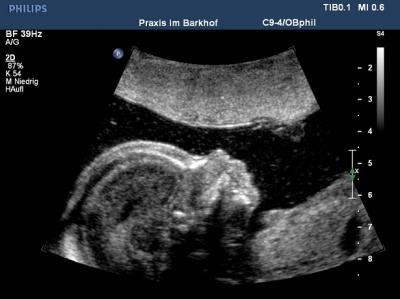

Ich kann durchweg positives Berichten :o) Mit unserem knirps ist alles bestens, gesund und munter. Ich berichte jetzt mal nciht zu ausführlich da man hier ja leider lauter traurige Geschichten liest/hört und ich niemanden noch tiefer verletzen möchte.. Bei uns wirds dieses mal ein Mädchen wir freuen uns wie verrückt :o) Der Doc war super nett und sehr gründlich, da hatten wir von Anfang an ein gutes Gefühl! Und weils so schön war darf ich im März als US-Model nochmal wieder kommen, bekomme ne kl. Aufwandsentschädigung uuuuuund 3D Bilder für Lau :o) Anbei ein US Bild und ein Bauchbild :o)

Bild zu FD heute mit Outing :o) - Forum für Juli - Mamis

Schicker Bauch, aber der Hit ist ja das süße Profil von deiner Kleinen. LG, Marie

Tolles bild von deiner Bauchbewohnerin ... und schicke Einraumwohnung hat die Kleine da Freut mich, dass alles iO ist bei euch... LG deine Keksi